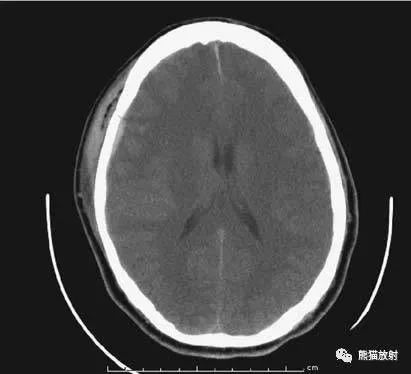

在胼胝体和侧脑室上方,大脑镰自前向后贯穿中线。白质部分为半卵圆中心,额叶范围缩小,顶叶所占比例扩大,枕叶基本消失。

- 半卵圆中心:位于胼胝体上方,由左右大脑半球髓质形成的有髓纤维,对称位于大脑镰两侧区域。